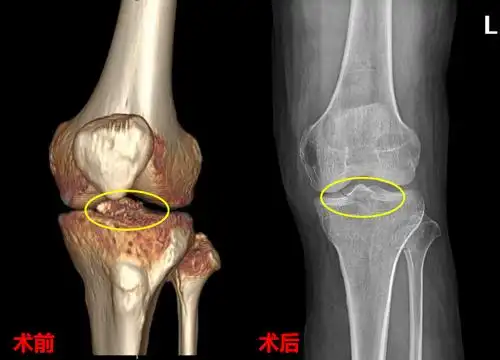

胫骨髁间棘骨折术前dr片!

胫骨髁间棘骨折

疼痛,肿胀,活动受限,在外院做膝关节x线检查发现是左侧胫骨髁间棘骨折